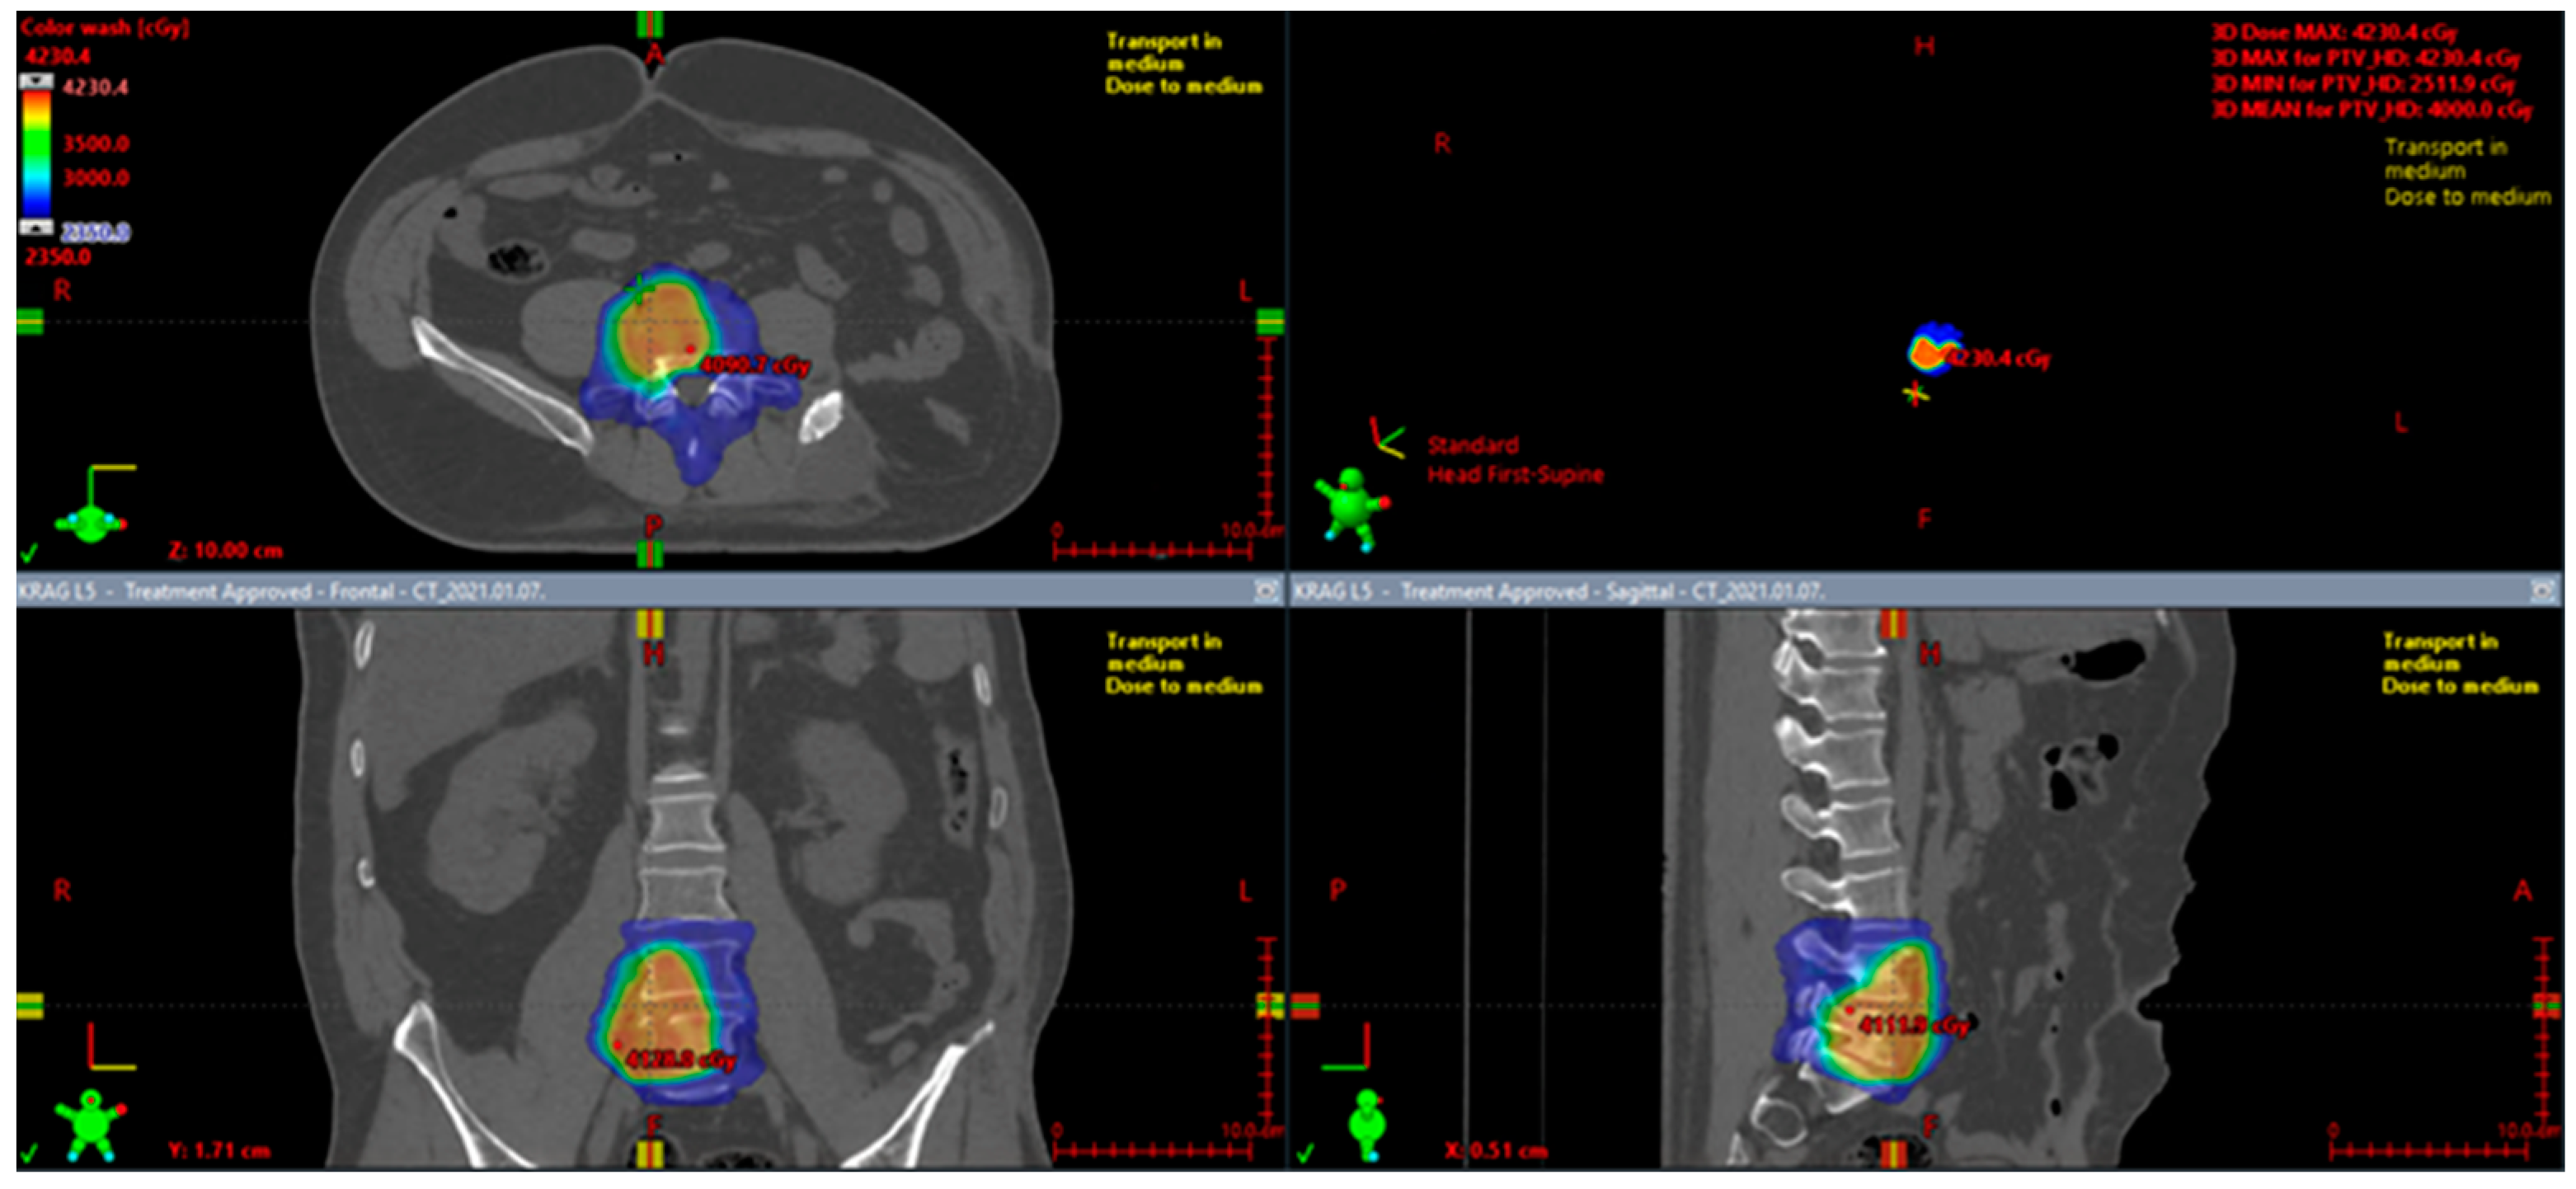

Figure 7.

Preoperative radiotherapy for a marginally resectable pelvic solitary fibrous tumor.

Figure 8.

Preoperative radiotherapy contrast-enhanced MRI image of the SFT of the right groin: (A) coronal image; (B) axial image.

Moreover, in the case of mediastinal SFTs with external invasion, postoperative radiotherapy may provide a substantial benefit in local control [174]. Some studies report a regain of resectability after preoperative radiotherapy [176,177]. Therefore, SFTs may not be as radioresistant as other soft tissue sarcomas. An example of preoperative radiotherapy in a marginally resectable pelvic SFT is presented in Figure 4. The patient received 50 Gy in 25 fractions.